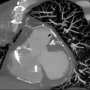

The patient’s hemoptysis and tachypnea improved after successful sealing of the perforation. No more hemoptysis was noted throughout the hospital course. Nevertheless, he developed an episode of abnormal liver function, which might be related to a lipid-lowering agent. The lipid-lowering agent was discontinued and the patient’s liver function was checked regularly during admission. He was discharged 16 days later, after the liver function had returned to normal. However, a 320-slice cardiac computed tomographic (CT) image did not show a direct contact between the perforated SVG and the lung parenchyma or bronchial trees (Figure 3).

Figure 3. Computed tomographic reconstruction image showing a thin layer of tissue between the SVG and lung parenchyma (arrowhead, stent graft) (click thumbnail to view larger image).

There have been only few reports on hemoptysis caused by an SVG aneurysm (SVGA) rupture previously.7-11 According to previous reports, the size of the ruptured SVGA ranged from approximately 2 to 5 cm. Three major different mechanisms are related to the hemoptysis caused by the rupture of an aneurysm. First, the aneurysm densely adherent to the lung had ruptured with bleeding into the pleura and lung parenchyma. Large hematoma eroding into the lung tissue could cause hemoptysis.9,10 Second, a fistula developed between a vein graft aneurysm and the bronchial trees.7,8 Hemoptysis is caused by bleeding from the aneurysm into a segmental bronchus. Third, the SVGA connected to lung parenchyma with no evidence of fistula.11 To our knowledge, this is the first report of such a case of hemoptysis after an SVG rupture due to coronary intervention. The cardiac CT image showed no evidence of fistula between the vein graft and a bronchus or the existence of direct connection between the proximal SVG and the lung parenchyma or bronchial trees. Only a thin layer of tissue between the SVG and lung parenchyma was noted from the CT reconstruction image; therefore, the SVG may be densely adherent to the lung. The coronary angiography revealed contrast extravasation with jet stream effect at the site of balloon dilation. Comparing the reconstructed CT image with the coronary angiographic image from a similar angle, we speculate that blood jet stream from the SVG graft perforation could have directly leaked into the lung tissue, causing the hemoptysis.